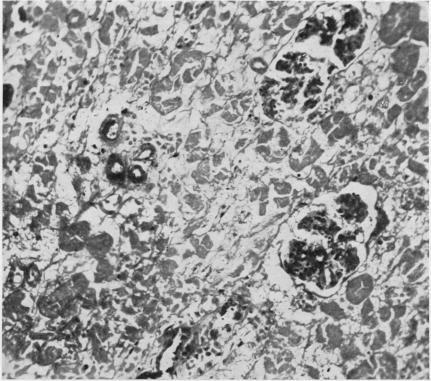

Distal tubular and proximal tubular necrosis in the kidneys of burned patients.